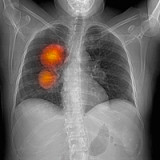

11.10.2019 Gesundheit, Schweiz Heftig umkämpfter Markt für Krebsmittel Roche und Novartis müssen sich sputen, um ihre Position in der Onkologie zu behaupten. Bei Immuntherapien könnten sie nun aber aufholen.